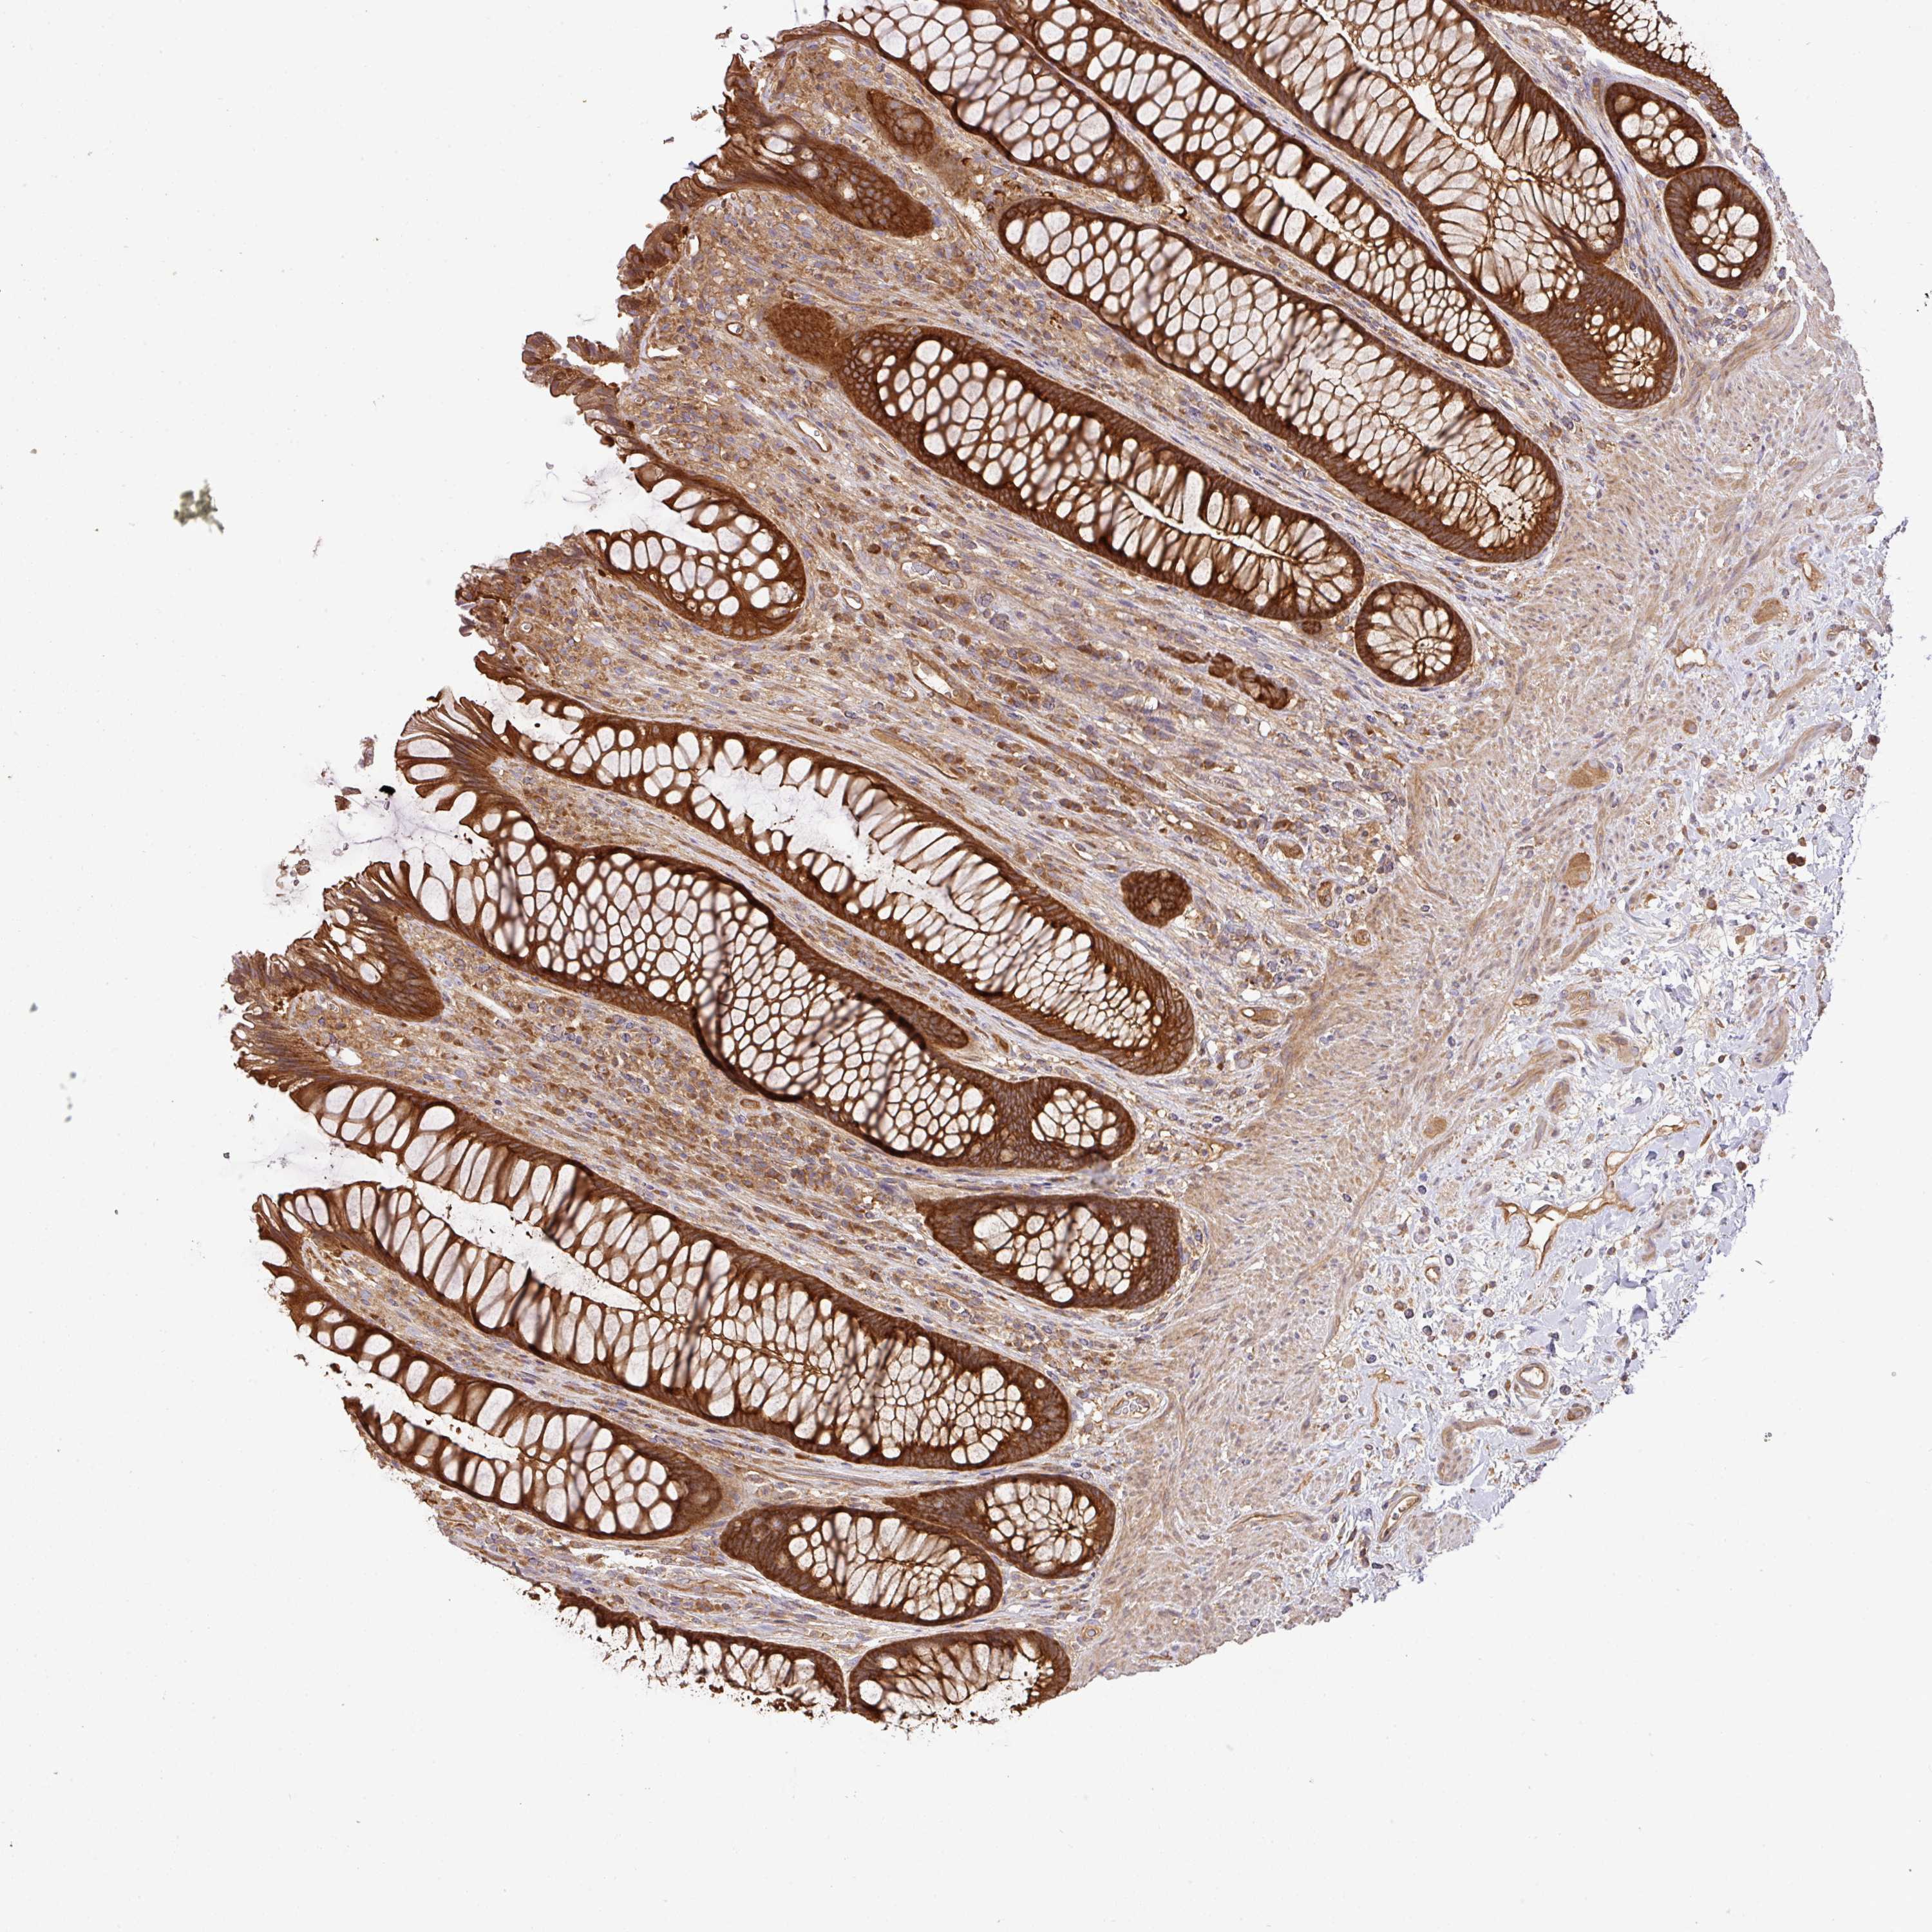

RECTUM - Antibody stainingi

Antibody staining in the annotated cell types in the current human tissue is reported as not detected, low, medium, or high, based on conventional immunohistochemistry profiling in selected tissues. This score is based on the combination of the staining intensity and fraction of stained cells. Each image is clickable and will lead to virtual microscopy that enables deeper exploration of all samples and also displays staining intensity scores, fraction scores and subcellular localization as well as patient and tissue information for each sample.

Antibody HPA052488

Glandular cells High